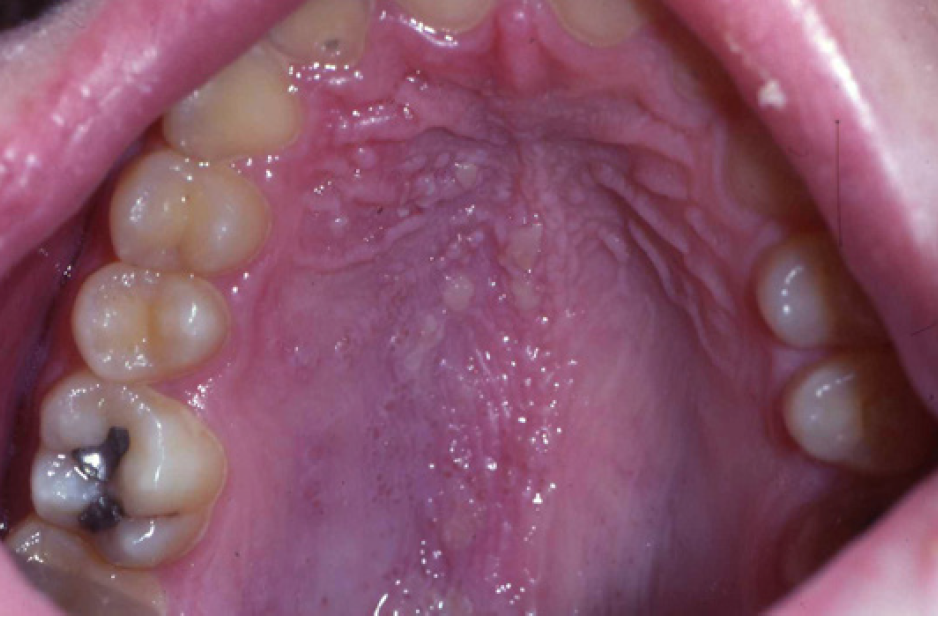

Neoplastic

Kaposi's Sarcoma (Figure 1). People with AIDS-associated Kaposi's sarcoma (KS) frequently have oral lesions that visually manifest as red, brown, or purple patches or swellings. The palate is the most common site but lesions also occur on the gingiva, tongue, and oropharynx. KS is usually asymptomatic, but occasionally becomes painful because of ulceration or infection. Bulky gingival lesions that show when the patient smiles or talks may be of concern for cosmetic reasons and may also interfere with oral hygiene. Good oral hygiene and professional prophylaxis is, therefore, important in the management of oral KS. Small, well-localized lesions on the palate or gingiva are usually good candidates for treatment with intralesional injection of vinblastine (a drug used in combination with chemotherapeutics to treat cancers). Surgical removal and the carbon dioxide laser are also sometimes useful in removing such lesions. Small lesions may be treated on several occasions to achieve the best results. Large lesions may respond better to radiation therapy, either in a one-dose treatment or fractionated treatments delivered for ten to twelve days. Some patients experience episodes of mucositis during chemotherapy and xerostomia is sometimes a problem, but usually improve after therapy. Systemic chemotherapy is indicated for widespread or disseminated disease.

Figure 1. Kaposi’s sarcoma, oral lesions (courtesy of dentalcare.com)

Figure 1